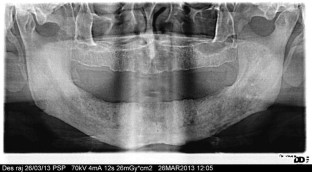

Fig. 3